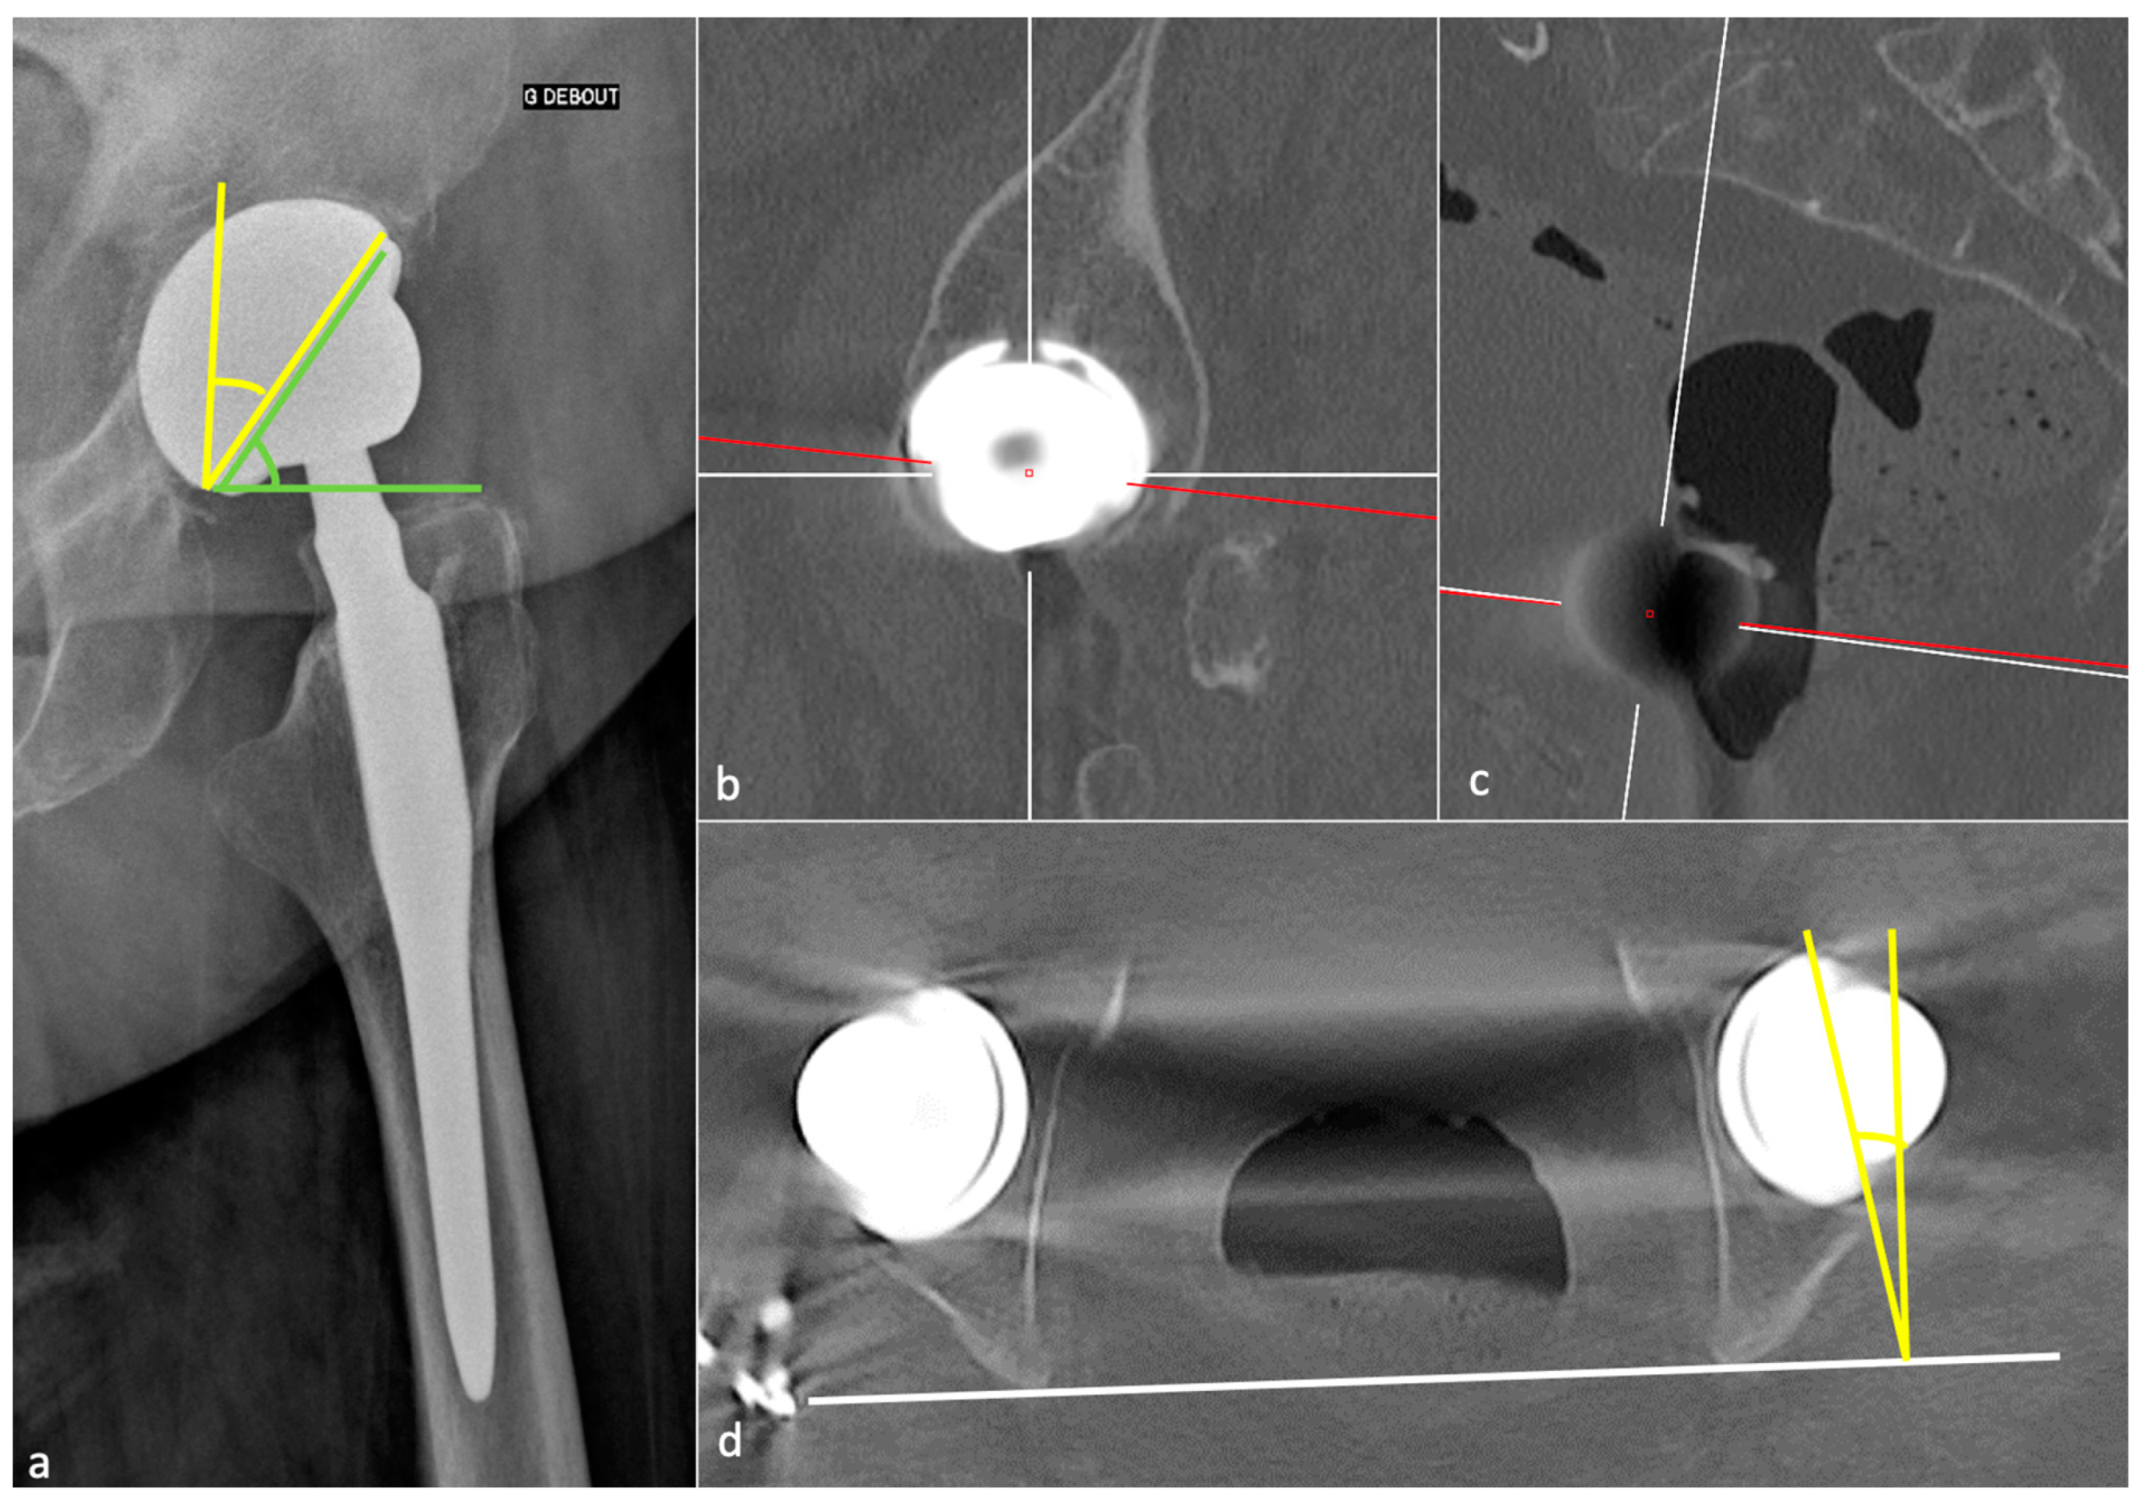

3.3.1. Acetabular Side

3.3.2. Femoral Side

4.2.2. Imaging